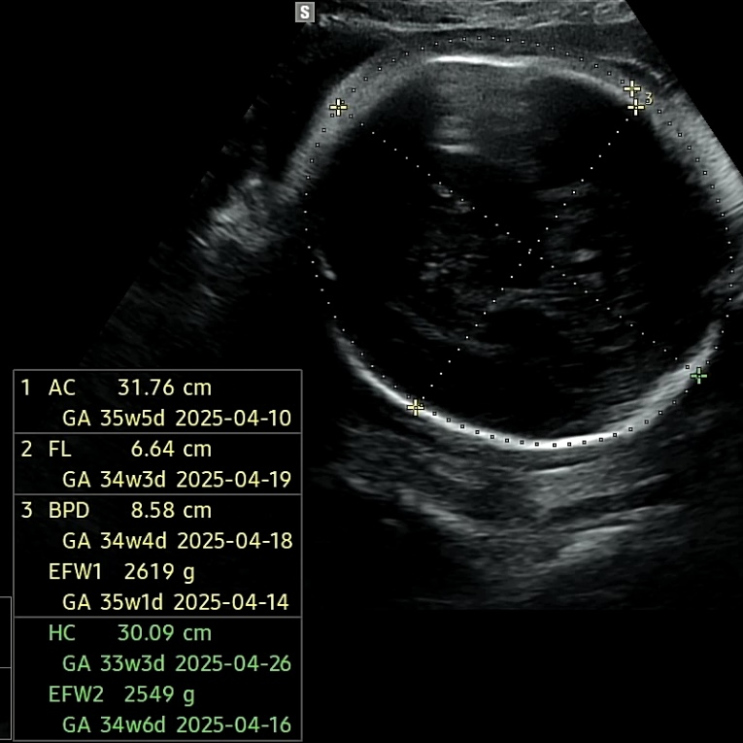

수박씨 마지막 정기검진 20여 분간의 태동 검사를 마치고, 초음파 검진을 받는데 아기가 3.3kg이 되어 분만...

임신39주 / 마지막 검진, 태동 검사, 유도분만일 결정

친한 친구들 중 몇 명이 37주에 이미 진통을 느껴 출산한 바 있기에 혹시 이번 주? 혹시 오늘? 하는 마음으...

임신 38주 / 만삭 증상, 내진, 3.05kg, 마지막 철분주사

임신 36주 / 태동검사, 철분주사, 백일해 주사

매일 아침 내 안에서 꿈틀거리는 생명력에 아득했던 정신이 돌아오는 순간을 즐기고 있다. 불룩해진 배가 ...